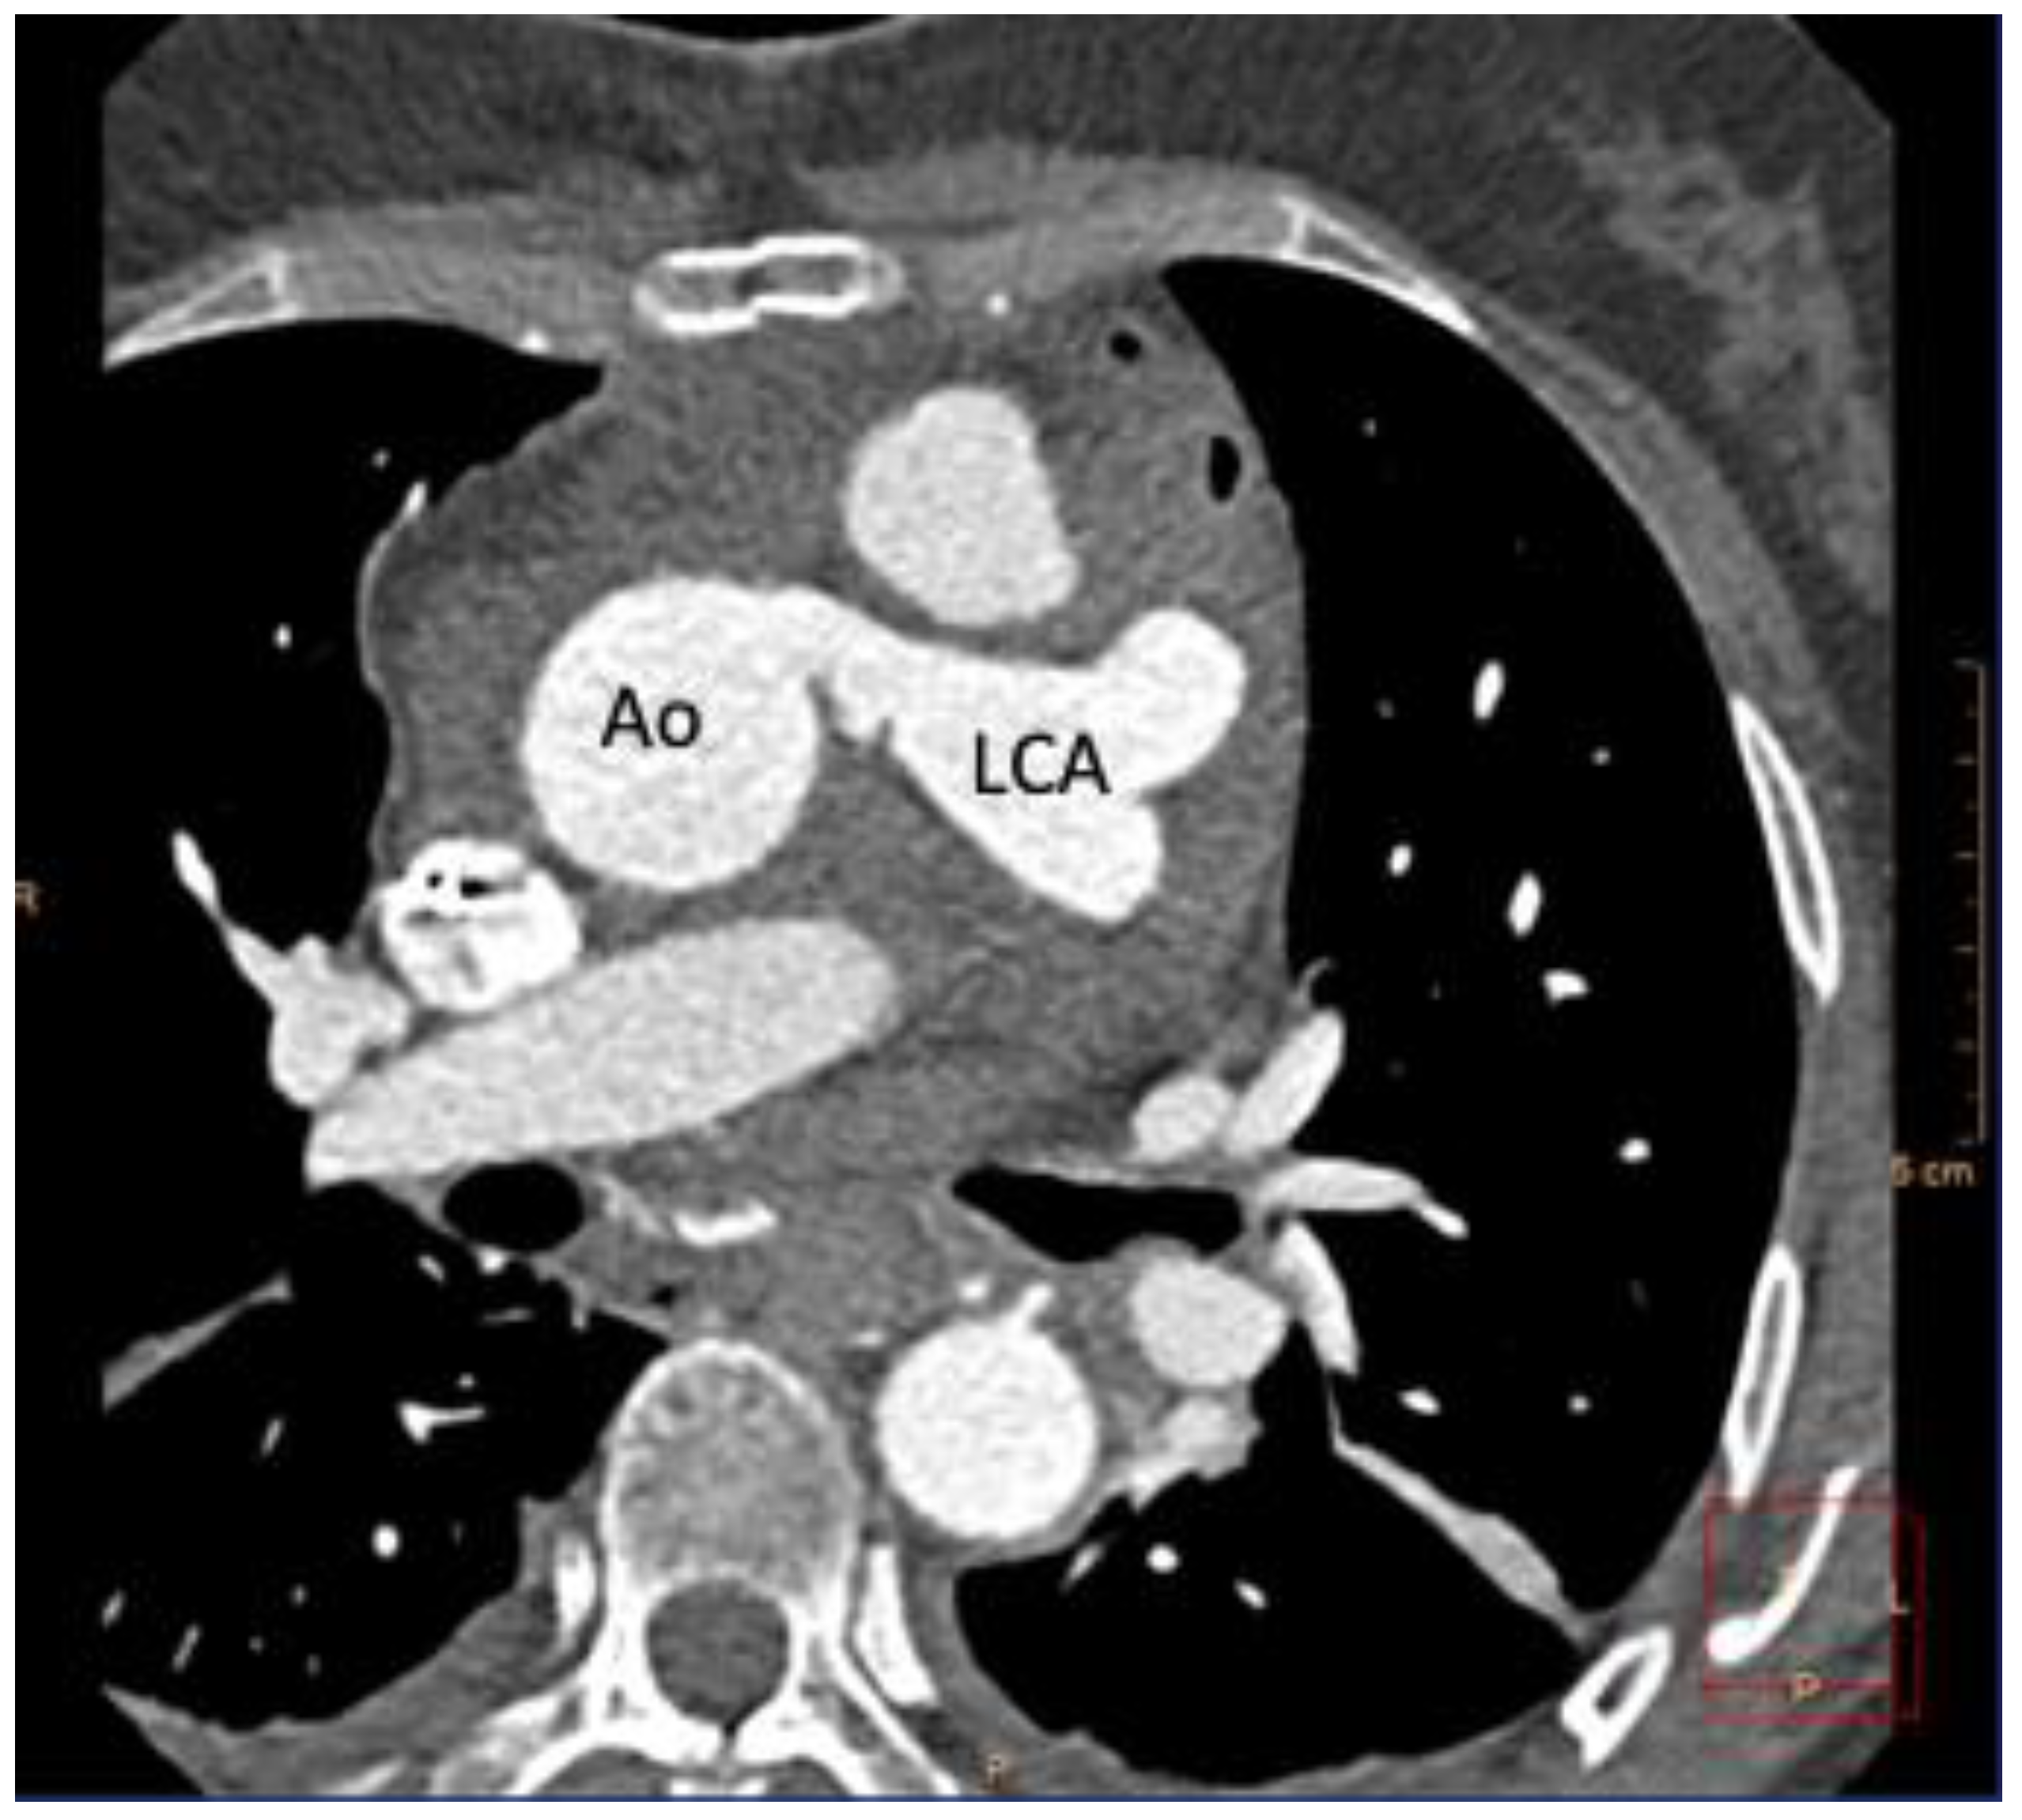

2. Case Report

Case Presentation